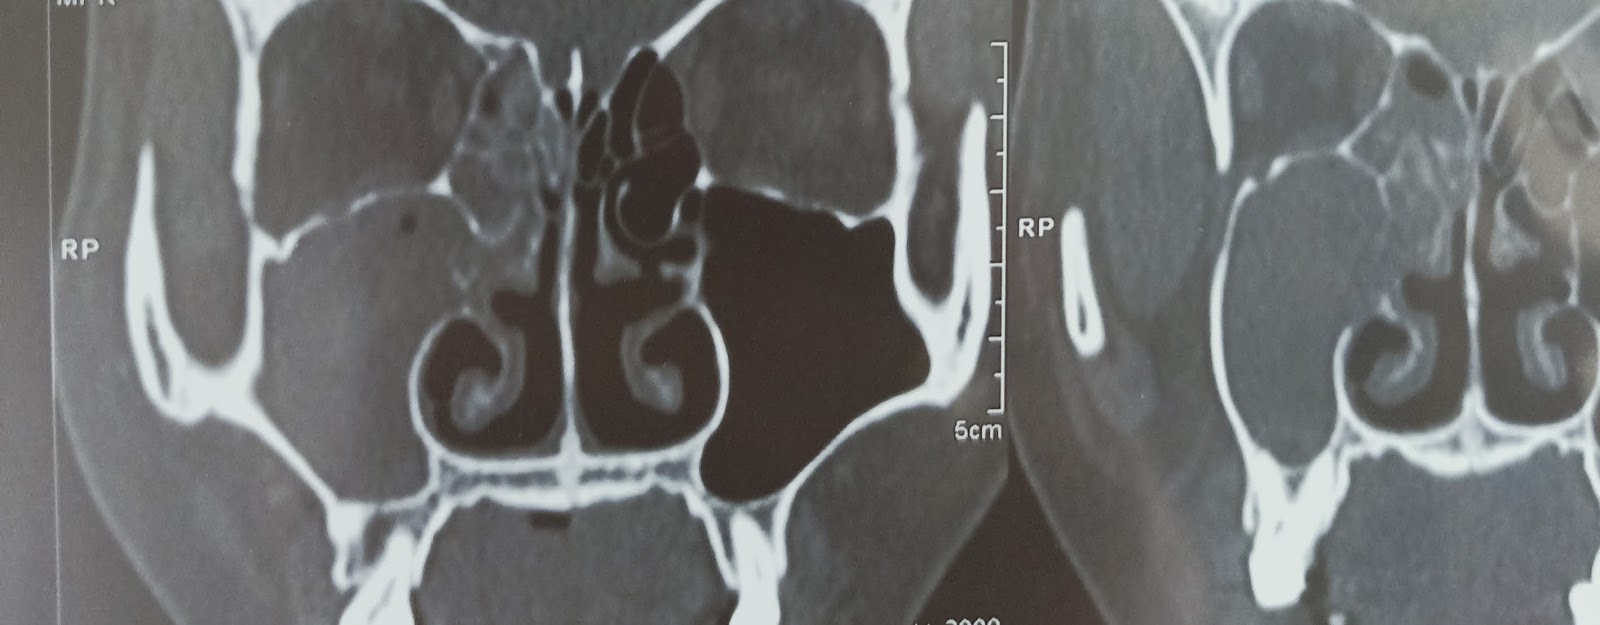

Có thể Bạn đã bị : Viêm xoang hàm do răng .